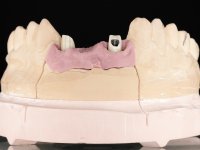

A exposição cirúrgica do implante e a colocação do parafuso de cicatrização mostrou-se uma surpresa negativa no que diz respeito à sua posição. Rejeitada a proposta de remoção do implante, avançamos para a sua reabilitação provisória. Foi feita a impressão por técnica de moldeira aberta e em laboratório foi confecionado um coto aparafusado com componente gengival e coronário e uma coroa em acrílico também com estes dois componentes. A coroa provisória foi colocada em boca até ser tomada uma decisão definitiva. Passaram 6 anos até que a paciente retorna à consulta com um abcesso no dente 1.1. Tomada a decisão de extrair os dentes 1.1 e 2.2 foi feita uma impressão para confecionar uma ponte provisória de 3 elementos com uma rede para ser aderida aos dentes adjacentes. A cirurgia foi planificada e realizada, colocando-se os dois implantes no local do 1.1 e 2.2 e o implante no local do 2.1 foi cortado com o objetivo de o submergir, simultaneamente foi feita a regeneração tecidular adequada (Trabalho Cirúrgico realizado por Dr. Manuel Neves). Durante a osteointegração a paciente utilizou a ponte provisória fixa. Foi realizada primeira impressão para a confeção de uma ponte provisória aparafusada em Zr que trabalhou durante 12 semanas os tecidos moles. A impressão definitiva foi feita com a individualização dos transferes. A reabilitação definitiva foi feita com cotos ceramizados e com uma ponte de infraestrutura em Zr revestida por cerâmica. Em virtude da inclinação do implante colocado no local do dente 1.1 a ponte exigiu fixação cimentada.